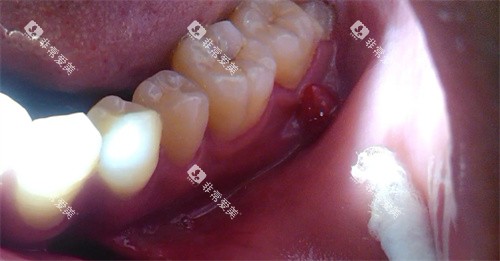

口腔治疗涉及到患者的口腔黏膜和血等,可靠卫生至关重要。

榆林市第一医院口腔科严格遵守消毒灭菌制度,对诊疗设备和器械进行严格的消毒处理,确保患者的治疗可靠。

在正规医院进行口腔治疗,可以有效避免交叉感染等问题。